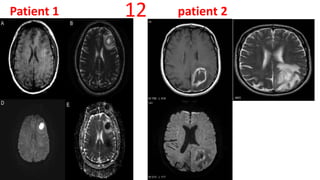

Patient 1 patient 212

Abscess vs GBM

• Capsule is isointense or hyperintense to white matter on T1 and hypointense on T2

• Area of Central Necrosis- Low signal on T1,high signal on FLAIR and T2 (low

density on CT)

• DWI - Restricted

• MRS :Central necrotic area shows alanine, succinate and acetate peaks

Necrotic Tumor vs. Pyogenic Abscess: Differentiation by DWI and ADC

• Necrotic Tumor: Decreased signal intensity on DWI. Increased signal

intensity on ADC maps

• Pyogenic Abscess :Increased signal intensity on DW I Markedly decreased

signal intensity on ADC maps